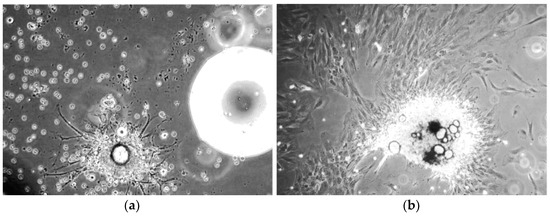

Further evidence of osteoblast differentiation was the morphological change associated with dexamethasone treatment.

Characteristics of the morphological change included the transition from spindle-shaped cells that formed densely populated colonies (Figure 4a) to polygonal cells with less densely packed colonies and enlarged cytoplasmic space (Figure 4b).

Figure 4. Phase contrast microscopy images of hBM-MSCs before and after dexamethasone treatment. (a) BM002 hBM-MSCs grown in the absence of differentiation stimuli, display spindle-shaped cells that formed densely populated colonies (100× magnification); (b) BM002 hBM-MSCs grown in the presence of differentiation inducing dexamethasone, display polygonal cells with less densely packed colonies and enlarged cytoplasmic space (100× magnification).